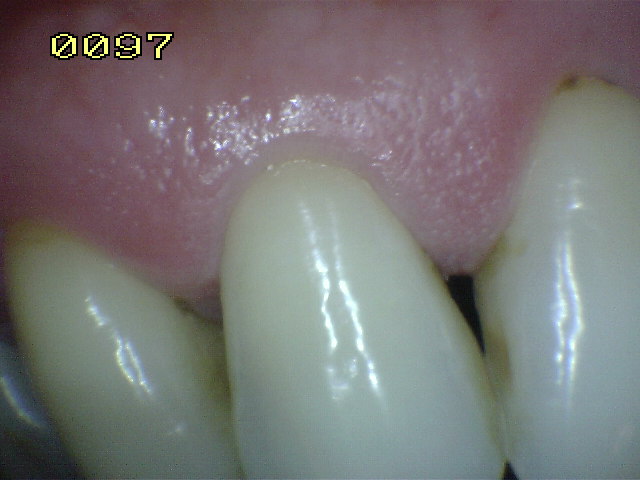

Encía Normal |

| Normal |

| Color |

Rosa pálido |

| Aspecto |

Puntillado, tipo piel de naranja |

| Consistencia |

Firme |

| Hemorragia |

Ausente |